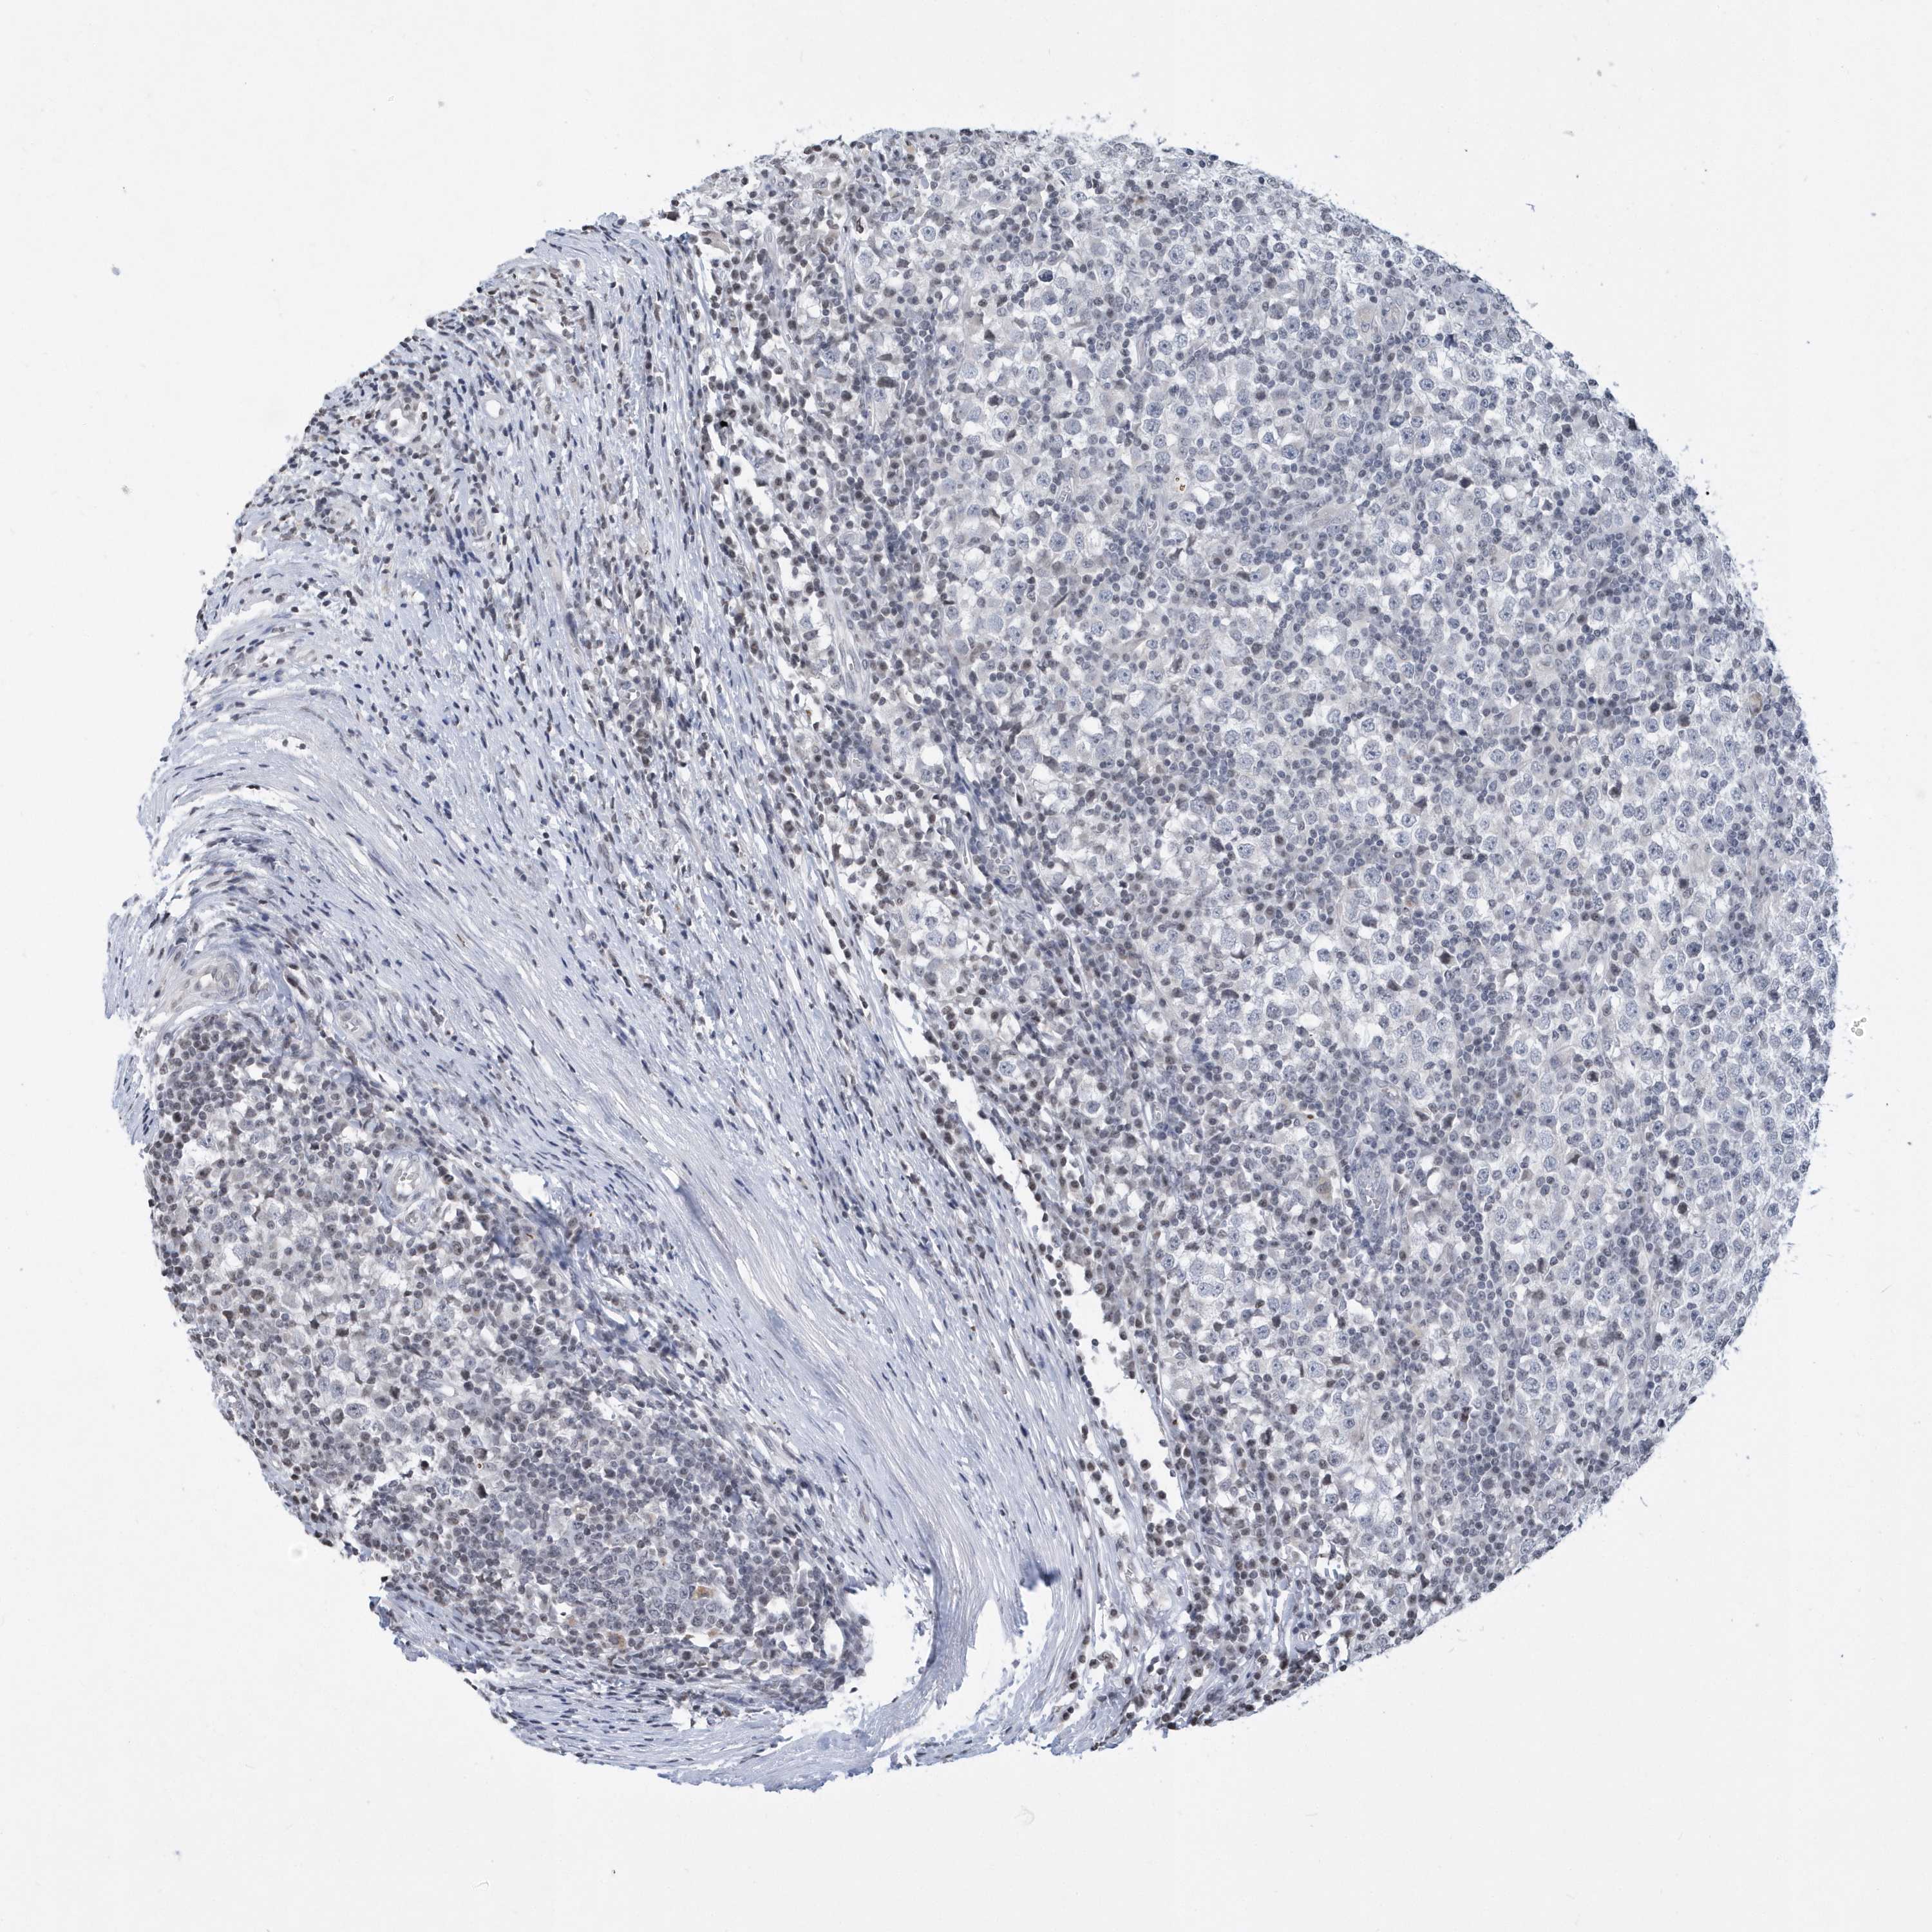

TESTIS CANCER - Protein expressioni

A mouse-over function shows sample information and annotation data. Click on an image to view it in a full screen mode. Samples can be filtered based on level of antibody staining by selecting one or several of the following categories: high, medium, low and not detected. The assay and annotation is described here.

Note that samples used for immunohistochemistry by the Human Protein Atlas do not correspond to samples in the TCGA dataset.

Antibody stainingi

Antibody staining in the annotated cell types in the current human tissue is reported as not detected, low, medium, or high, based on conventional immunohistochemistry profiling in selected tissues. This score is based on the combination of the staining intensity and fraction of stained cells.

Each image is clickable and will lead to virtual microscopy that enables deeper exploration of all samples and also displays staining intensity scores, fraction scores and subcellular localization as well as patient and tissue information for each sample.

Antibody HPA036823

Antibody HPA036824

Antibody HPA061412

Carcinoma, Embryonal, NOS

Seminoma, NOS

Urothelial carcinoma, High grade

Teratoma, malignant, NOS